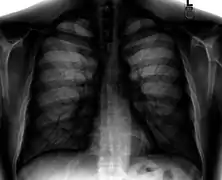

A chest radiograph, called a chest X-ray (CXR), or chest film, is a projection radiograph of the chest used to diagnose conditions affecting the chest, its contents, and nearby structures. Chest radiographs are the most common film taken in medicine.

Like all methods of radiography, chest radiography employs ionizing radiation in the form of X-rays to generate images of the chest. The mean radiation dose to an adult from a chest radiograph is around 0.02 mSv (2 mrem) for a front view (PA, or posteroanterior) and 0.08 mSv (8 mrem) for a side view (LL, or latero-lateral).[1] Together, this corresponds to a background radiation equivalent time of about 10 days.[2]

Chest radiographs are used to diagnose many conditions involving the chest wall, including its bones, and also structures contained within the thoracic cavity including the lungs, heart, and great vessels. Pneumonia and congestive heart failure are very commonly diagnosed by chest radiograph. Chest radiographs are also used to screen for job-related lung disease in industries such as mining where workers are exposed to dust.[3]